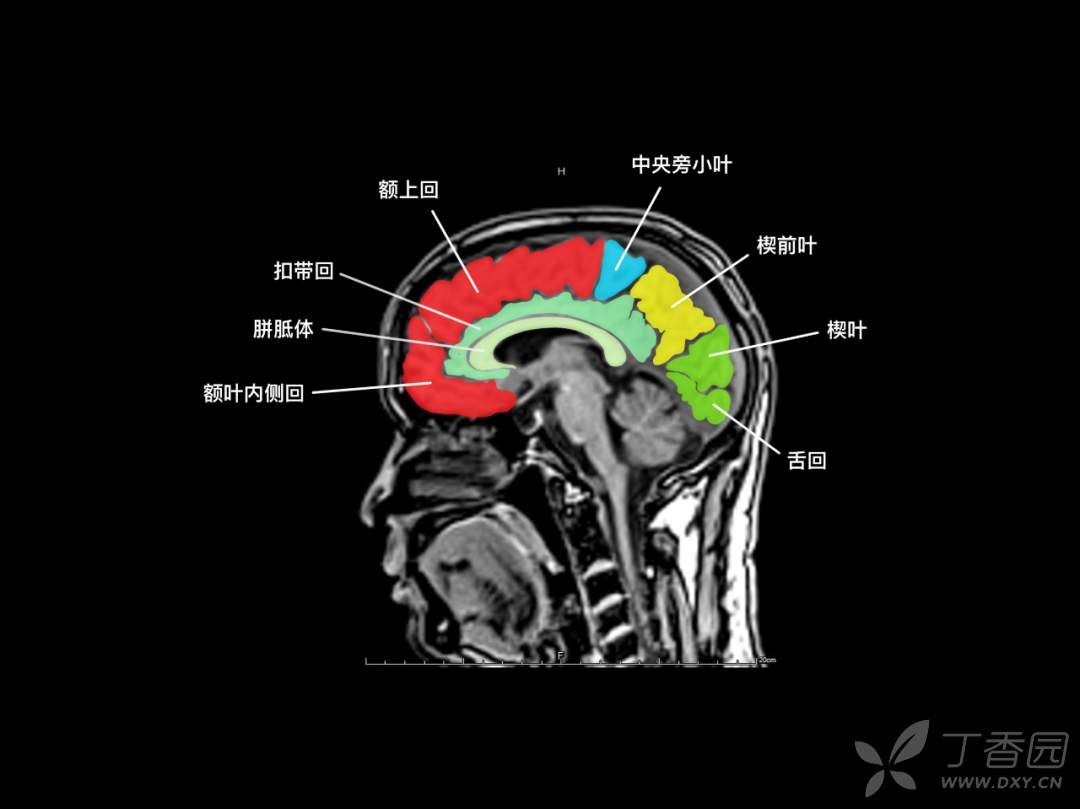

神经专业,要求「定位和定性」,先定位,后定性。与 CT 相比,颅脑 MR 可以更多、更清晰的呈现脑组织的解剖结构,神经专业的医生如何在颅脑 MR 的断层成像上去定位?

要么,你有「超级大脑」可以一层层的去记忆,「太难了」!那你也许会喜欢基于 「keypoint」的阅片方法,比如「苹果」外形、「Ω 征」、「M 征」等。本篇精华版 essay 希望给大家带来不一样的 MR 阅片技巧。

神经内科存在很多“征”,有助于帮助大家记忆!